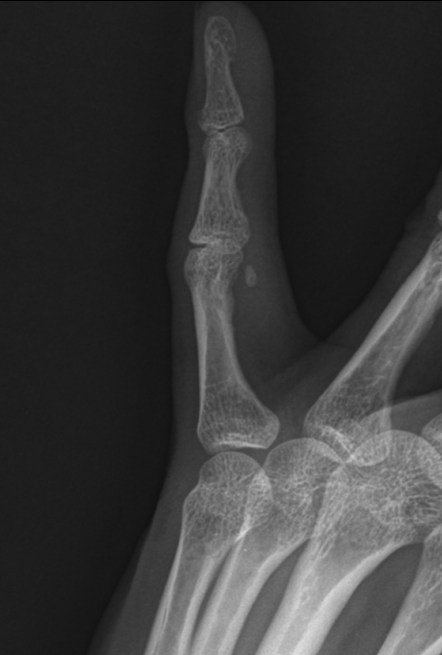

Subject   손가락을 삐엇다고 생각했는데.. 수술해야 할까요?

어제 밤에 얼음꺼내다 냉장고 문에 새끼손가락을 삐엇습니다.

x-ray상에선 작은 뼈조각이 떨어져나간게 보이는데 수술해야 할까요?

건열골절, 근위지골, 그위지관절의 요골촉부위, 5수지, 좌측